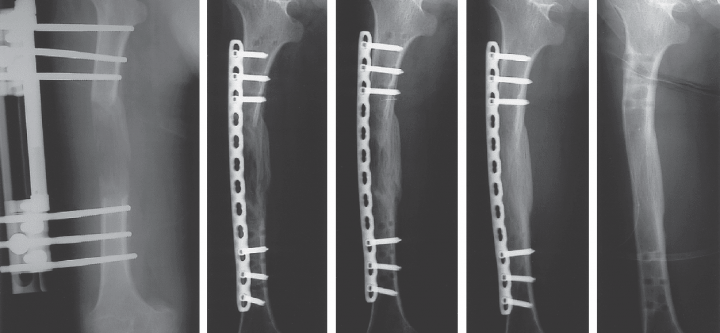

Ilizarov (ring) fixator

Ilizarov (ring) fixator What Is the Ilizarov Fixator? The Ilizarov fixator is a special type of external frame used in orthopaedic surgery to treat complex bone problems. It consists of rings, wires, and rods that surround the limb and hold the bone in place from the outside. Developed by Dr.…